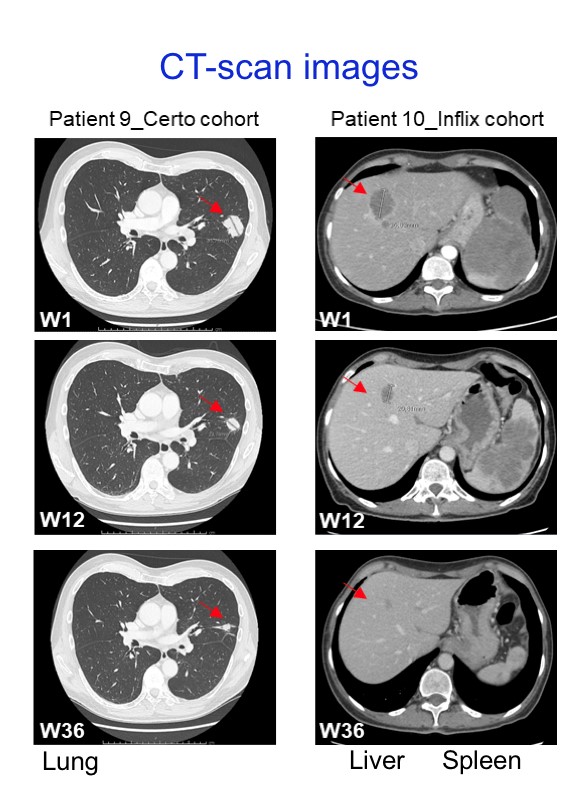

Illustration :

La trithérapie associant les inhibiteurs de points de contrôle immunitaire et les anti-TNF induit des régressions de métastases chez les patients atteints de mélanome cutané (Extrait de Montfort et al., Clin. Cancer Res. 2021) / Triple therapy with immune checkpoint inhibitors and anti-TNF drugs induces regression of metastases in patients with cutaneous melanoma (From Montfort et al., Clin. Cancer Res. 2021)